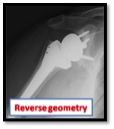

In some patients the tendons of the rotator cuff are damaged; if this is the case a reverse geometry shoulder replacement can restore excellent function in what would otherwise be a useless, painful shoulder. (see shoulder arthritis)